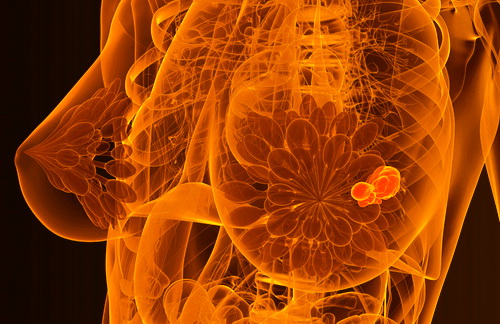

Как ожирение и проблемы с сердцем увеличивают риск рака молочной железы

Как ожирение и проблемы с сердцем увеличивают риск рака молочной железы

Избыточный вес способствует развитию гормональных нарушений, особенно касающихся эстрогенов, основных женских половых гормонов. Жировая ткань производит дополнительные количества эстрогена, который оказывает стимулирующее действие на клетки груди, способствуя их ускоренному росту и увеличению риска злокачественных изменений. Женщины с избыточным весом имеют повышенный уровень инсулиноподобного фактора роста (IGF-1), что также стимулирует рост клеток, включая раковые.

Кроме того, ожирение связано с хроническими воспалительными процессами, усиливающими окислительный стресс в организме. Это ведет к повреждению ДНК и повышению вероятности мутаций, провоцирующих развитие опухолей.

Сердце играет ключевую роль в поддержании нормального кровоснабжения тканей организма, обеспечивая доставку кислорода и питательных веществ. Проблемы с сердцем снижают эффективность кровообращения, приводя к ухудшению питания органов и тканей, включая молочные железы. Хроническая ишемия молочных желез увеличивает риски онкологических заболеваний, поскольку недостаток кислорода вызывает гипоксическое повреждение клеточных структур и повышает активность факторов ангиогенеза, участвующих в развитии опухоли.

Высокое артериальное давление, атеросклероз сосудов и нарушения сердечного ритма дополнительно ухудшают кровообращение и создают условия для прогрессирования патологического процесса.

Таким образом, ожирение и болезни сердца представляют собой комплексные факторы риска, существенно увеличивающие вероятность возникновения и прогрессирования рака молочной железы. Регулярная физическая активность, правильное питание и контроль веса помогают снизить этот риск.